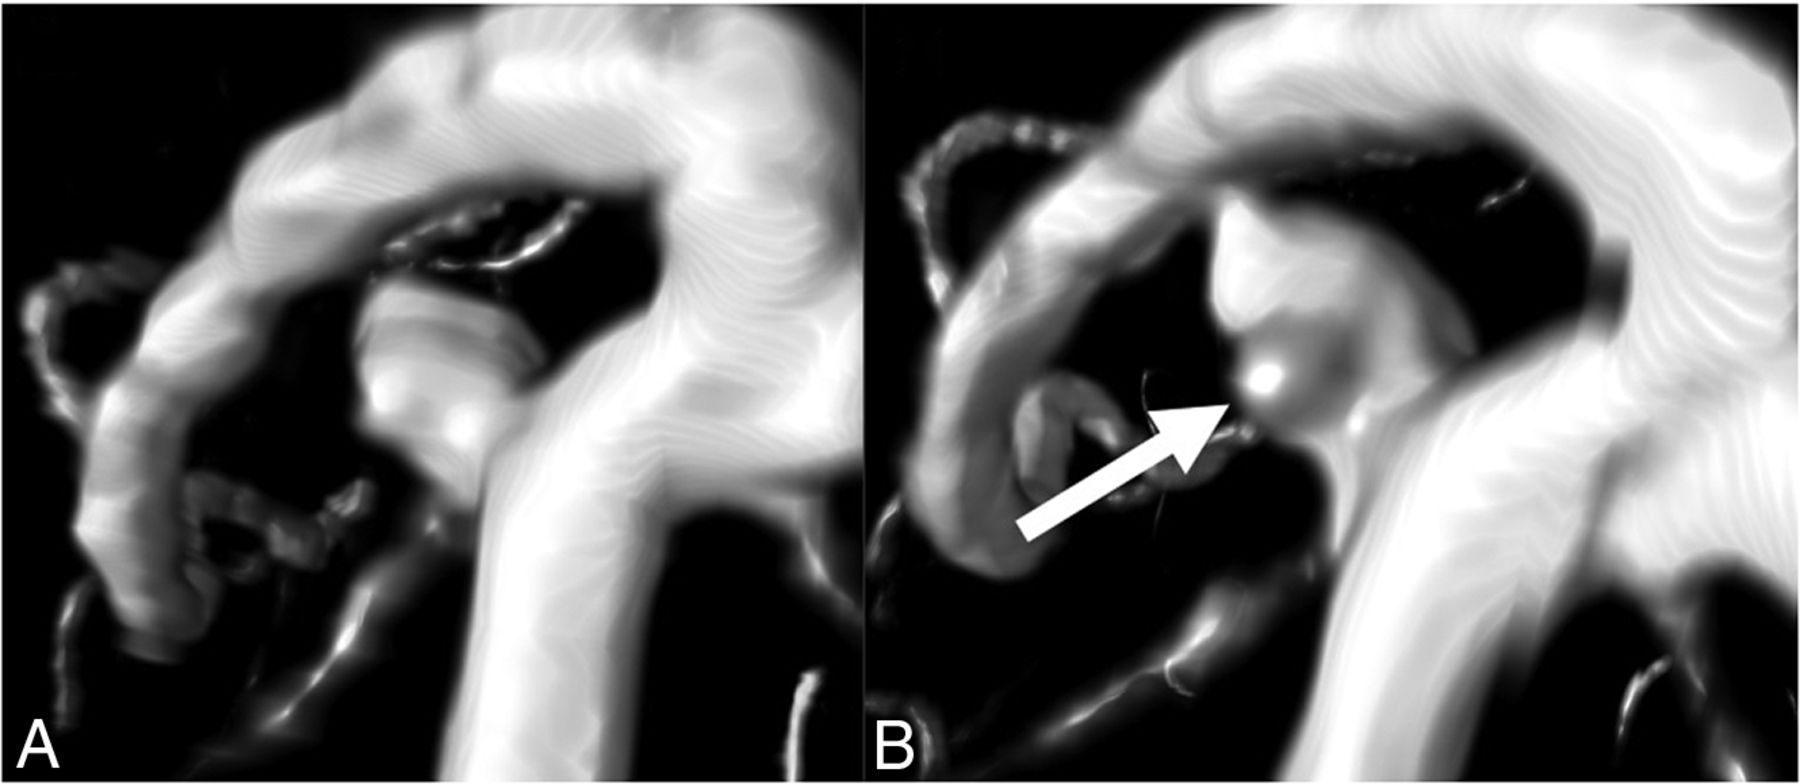

Shape index and curvedness. Shape index and curvedness values vary in 3D shapes. The shape index is a descriptor of the local shape of the surface of an object and is scale-invariant. Shape index values range from –1 (concave “cup”) through 0 (saddle point) to 1 (convex “dome”). The curvedness is a positive value to the local curvature of the surface, which usually lies between 0 and 1 and is dependent on the local scale of the object. These values are rotation- and translation-invariant.

To make 3D quantified morphology measurements of the UIAs, we manually segmented the UIAs from the original TOF-MRAs using in-house-developed software implemented in MeVisLab (MeVis Medical Solutions). All annotations were made by drawing a contour around the UIA on axial slices of the original TOF-MRA by the neuroradiologist who made the 2D measurements. The annotation did not include the parent vessels. Annotations were first made on the baseline scan, followed by the follow-up scan of the same patient. The annotations were converted to binary masks in which voxels that were located >50% inside the contour were labeled as UIAs. The images and annotations were all resampled to the median voxel size of 0.357 × 0.357× 0.500 mm. Using a marching cubes algorithm,19 we automatically fitted a mesh to the outside of the segmented UIA. The volume and surface area of the UIA were determined on the basis of the mesh around the segmented UIA. 3D volume change was determined as the difference in volume between the follow-up and baseline scans. The size of the UIA was determined by performing principal component analysis on the voxels within the segmented UIA and calculating the major, minor, and least extent. From these values, various morphology measurements were calculated on the basis of definitions in accordance with the IBSI guidelines,13 including compactness 1, compactness 2, elongation, flatness, and sphericity. Compactness 1 and 2 and sphericity are different measures that all quantify how similar the morphology of the UIA is to a sphere. Elongation describes the eccentricity of the UIA by describing how long it is relative to its width. Flatness quantifies the amount the UIA is flat relative to the length. Next, on the basis of the generated 3D mesh, the mean and Gaussian curvature of the surface of the UIA was determined, allowing the principal curvatures k1 and k2 to be calculated. By means of these principal curvatures, it was possible to determine the shape index and curvedness (Fig 1).20 Shape index and curvedness were calculated for every point on the mesh, and a median over the whole mesh of the UIA was determined. The shape index is a descriptor of the local shape of the surface of an object and is scale-invariant. The curvedness is a positive value, which describes the local curvature of the surface and is dependent on the local scale of the object. These values are rotation- and translation-invariant, and Fig 1 depicts examples of how these values vary.